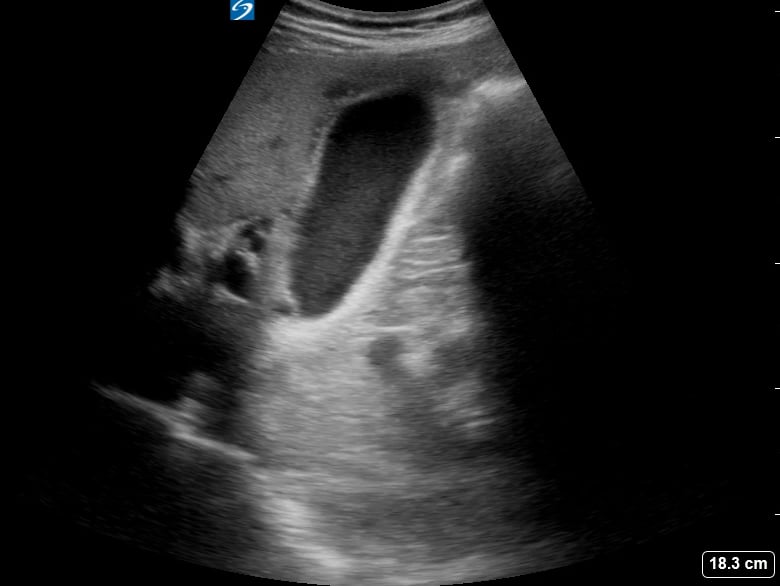

Pericholecystic fluid

Pericholecystic fluid, in abdominal ultrasound, refers to an abnormal collection of fluid surrounding the gallbladder. Its presence is a key indicator of gallbladder inflammation, commonly seen in acute cholecystitis, a condition causing severe abdominal pain. Sonographers meticulously assess this fluid for its location, amount, and characteristics to aid in accurate diagnosis.

This fluid accumulation is a crucial diagnostic sign for healthcare professionals. Early detection via ultrasound helps guide timely medical intervention and treatment strategies, preventing further complications related to gallbladder disease and improving patient outcomes in abdominal imaging.